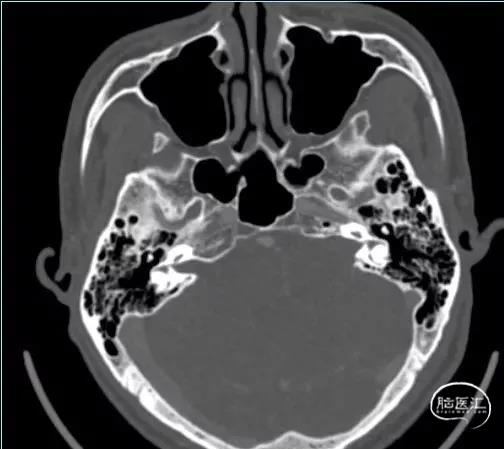

术前影像资料

扩大的内听道